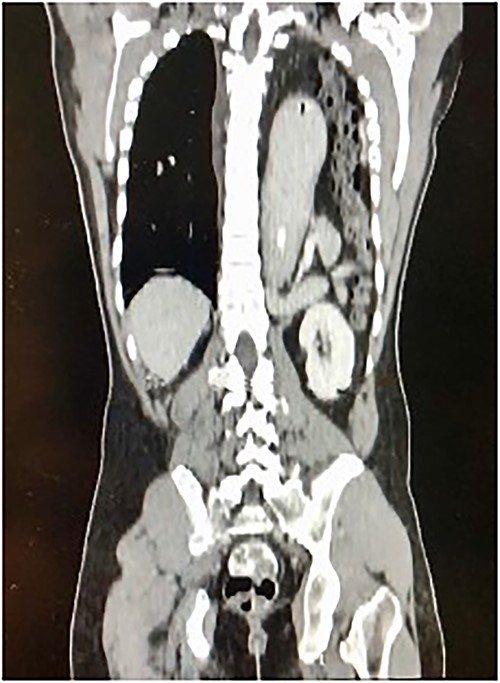

A 30-year-old male patient presented with a 1-week history of intermittent fever, generalized abdominal pain, vomiting, and coughing. He had been complaining of multiple episodes of choking sensation for several years which was treated as peptic ulcer disease. His past medical and surgical history were unremarkable with no previous history of trauma. On examination, he was tachycardic with a low grade fever. There was reduced left sided chest expansion with reduced breath sounds on auscultation. Interestingly, bowel sounds were heard over the left chest. On palpation of the abdomen, the left hypochondrium was tender and guarded. A Computed Tomography (CT) scan of the thorax and abdomen was done and showed a large left posterolateral diaphragmatic defect with herniation of the stomach, mesenteric fats, spleen, pancreatic tail, and bowel into the left hemithorax with mesenteroaxial gastric volvulus (Fig. 1). An exploratory laparotomy revealed a large posterolateral defect in the left hemi-diaphragm through which herniation of viable intraabdominal contents occurred. The contents were reduced into the intraabdominal cavity and the defect was repaired using composite mesh anchored with prolene 2/0 suture (Fig. 2). The patient made an uneventful post-operative recovery.

Longitudinal thoraco-abdominal CT scan shows protrusion of stomach, small and large bowel through a left posterolateral hemi-diaphragmatic defect.